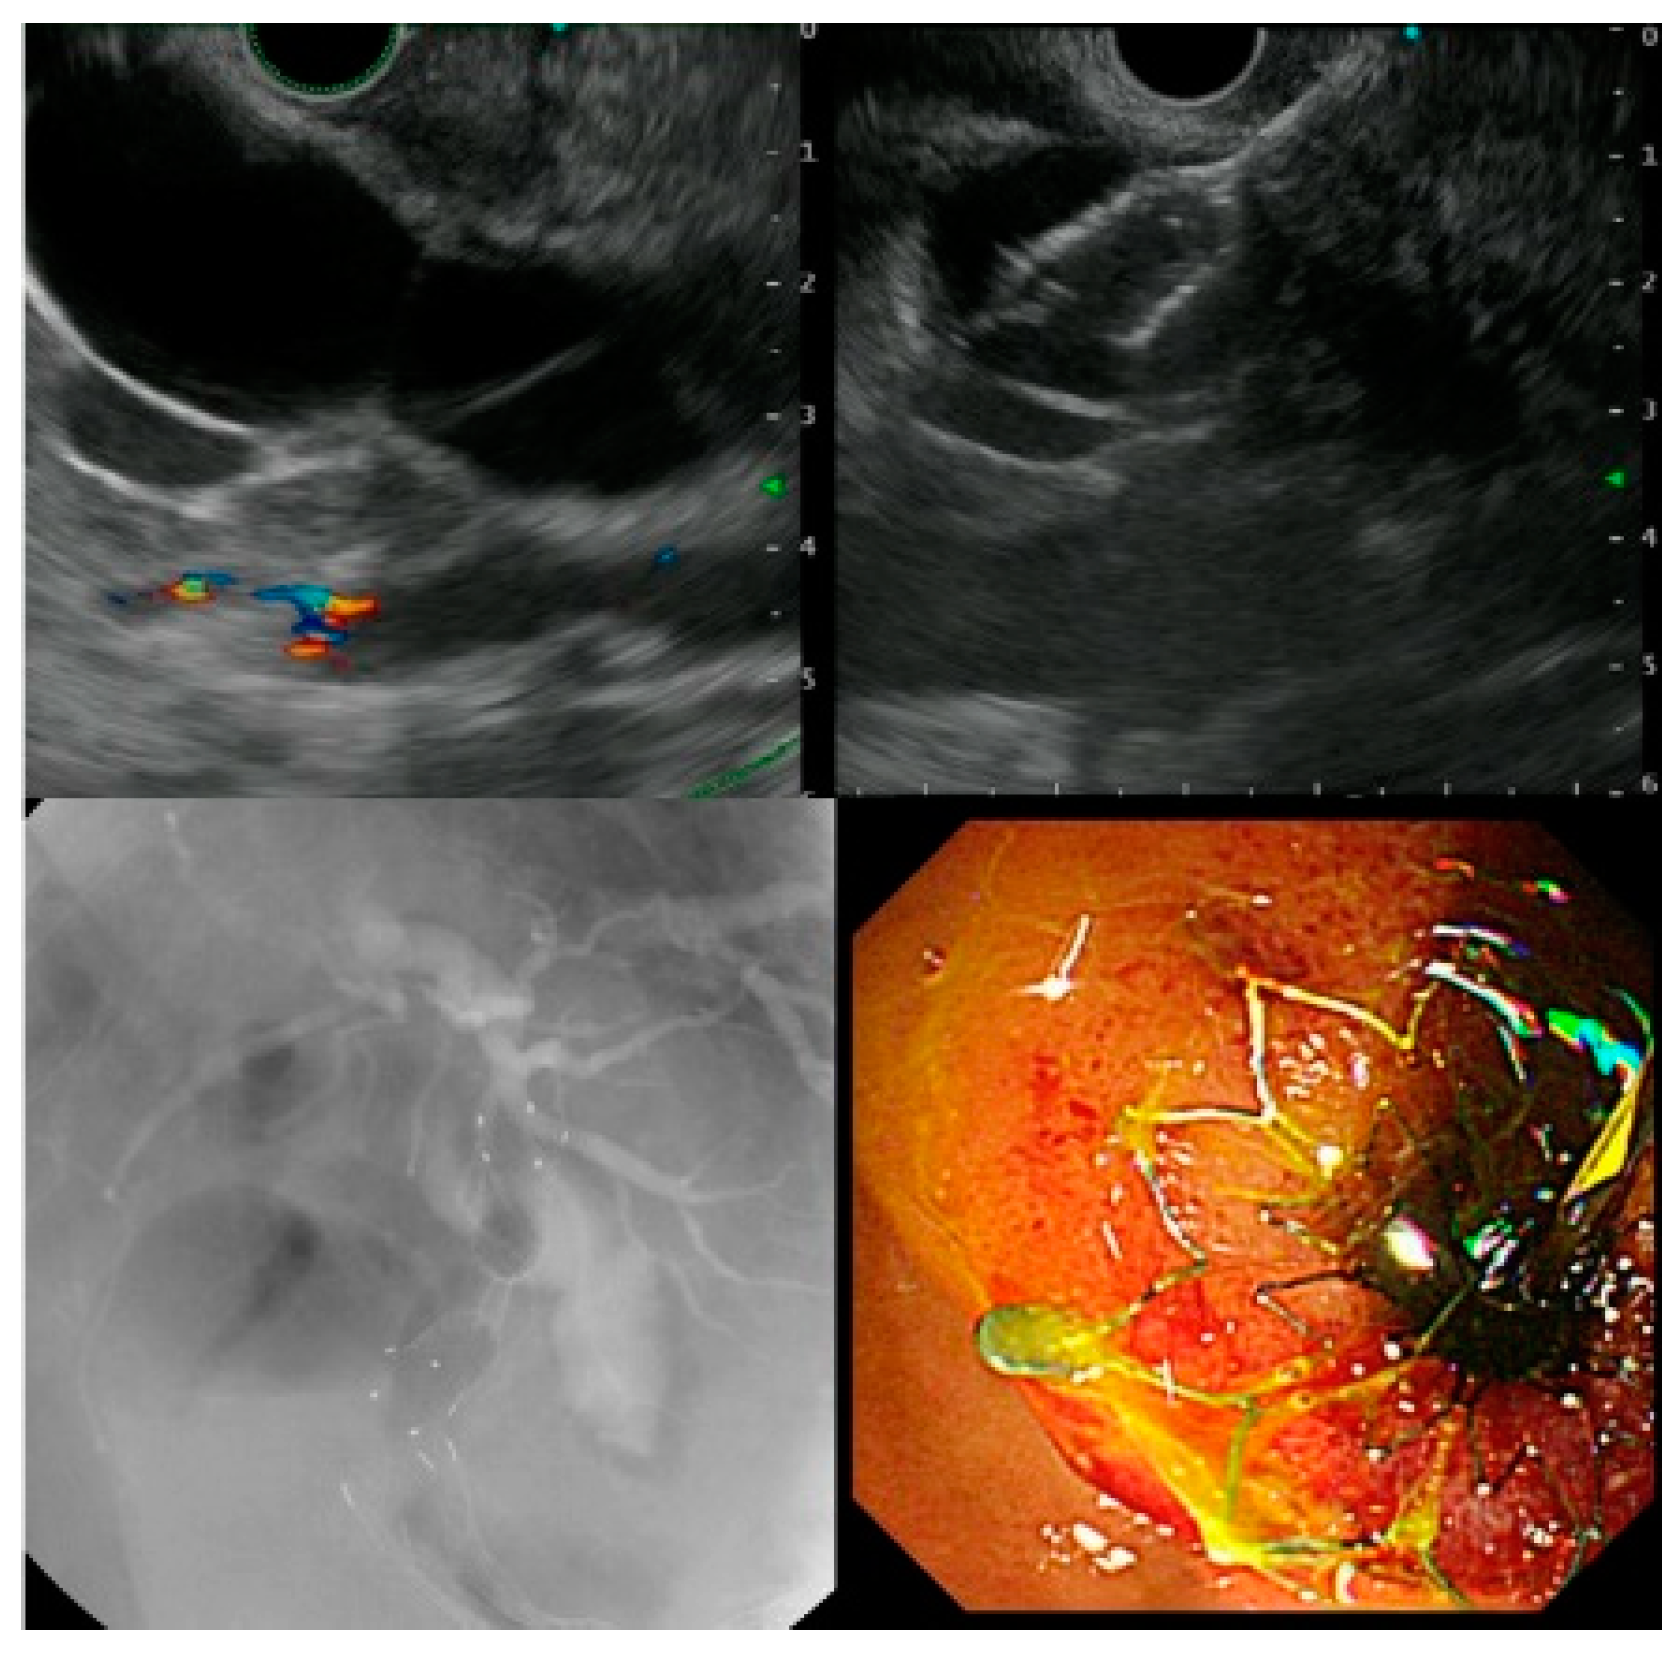

Consecutive steps of endoscopic ultrasound (EUS)guided transmural Endoscopic Gallbladder Drainage Transpapillary gallbladder drainage is an important option for inoperable patients requiring treatment of acute cholecystitis. Endoscopic drainage of the gallbladder can be established through the transpapillary route (i.e., through the papilla of vater, guided by endoscopic retrograde. Endoscopic gallbladder drainage can be performed to treat acute cholecystitis in cirrhotic patients and can serve as a bridge to liver transplantation. Endoscopic Gallbladder Drainage.